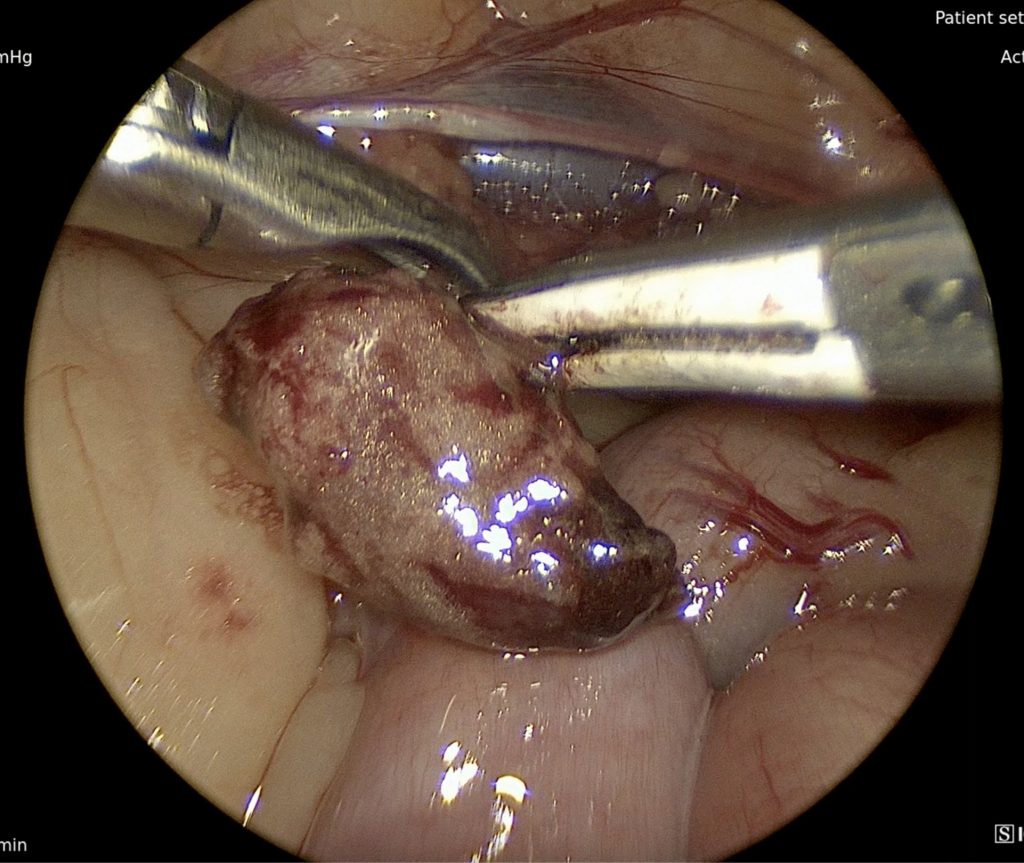

Splenectomy is a common procedure performed for associated masses, torsion, and adjunctive treatment of immune-mediated or infiltrative disease. Owners are often faced with a decision to move forward with a splenectomy for non-hemorrhagic splenic tumors encountered on imaging for a diagnosis. Although fine needle aspiration (FNA) can be performed, true diagnosis of pathology can only be achieved via biopsy. In the face of possible aggressive neoplasia with limited survival time, laparoscopic-assisted (Figures 4 and 5) or total laparoscopic splenectomy is attractive to owners, as it offers quicker recovery time and less post-operative pain.

Figure 4. Photograph depicting a laparoscopic-assisted splenectomy using a Ligasure vessel sealing device and an Alexis wound retractor device. Photo courtesy Dr. Ashley Villatoro

Figure 5. Photograph of the same patient depicting the large size of the spleen compared to the small incisional size. Photo courtesy Dr. Ashley Villatoro

A study of 136 dogs undergoing laparoscopic splenectomy had a low percentage of major complications, morbidity, and mortality. Conversion rates are reported to range from 0 to 5.9 percent for laparoscopic-assisted splenectomy.20 Single-port laparoscopic splenectomy has been reported and is feasible for smaller masses (3-4 cm) in smaller-sized dogs (<20 kg).21 Laparoscopic splenectomy is not feasible for a hemorrhaging splenic-associated mass or larger diameter-sized masses.22